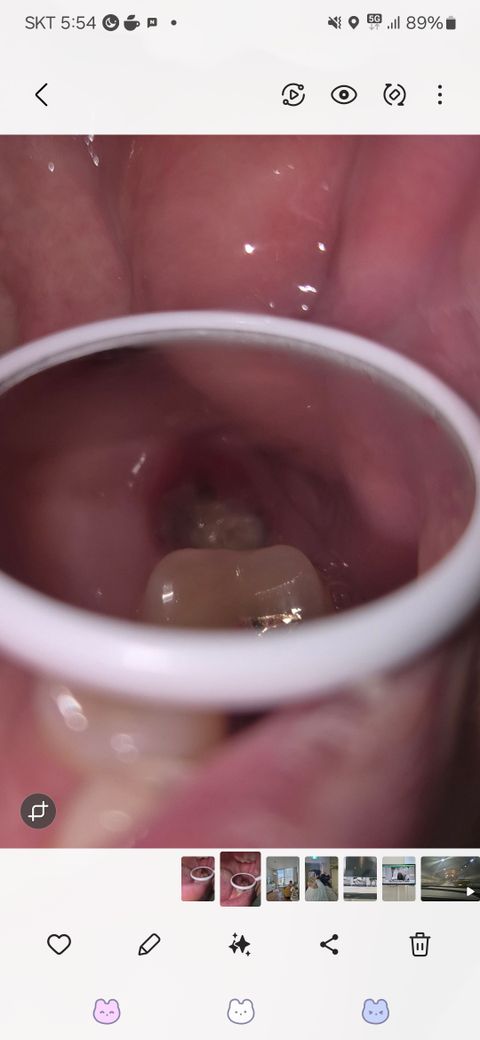

상악 어금니 발치후 노란덩어리 염증일까요?

상악 어금니발치하고 2주되었습니다.

치경으로 보니 구멍안에 저렇게 노란 덩어리가 생겼는데,염증 증상일까요??

• 3번 째 사진

정상적으로 아물고 있습니다. 잇몸 부위에 하얗게 딱지 앉은 것으로 보면 됩니다. 밑에서 살이 차올라 오면 없어집니다.